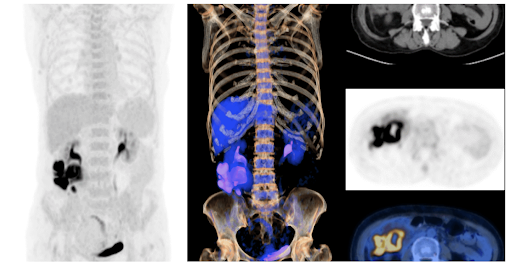

1. Faster Scans, Better Precision : Our new digital 160 slice PET CT scan is upto 70% faster than conventional systems, providing you with quicker, more efficient results with exceptional image quality

8 minutes Whole-body Scan

40.3 BMI Patient Imaging

0.05mCi/kg FDG Imaging

2.2mm small Lesion detection